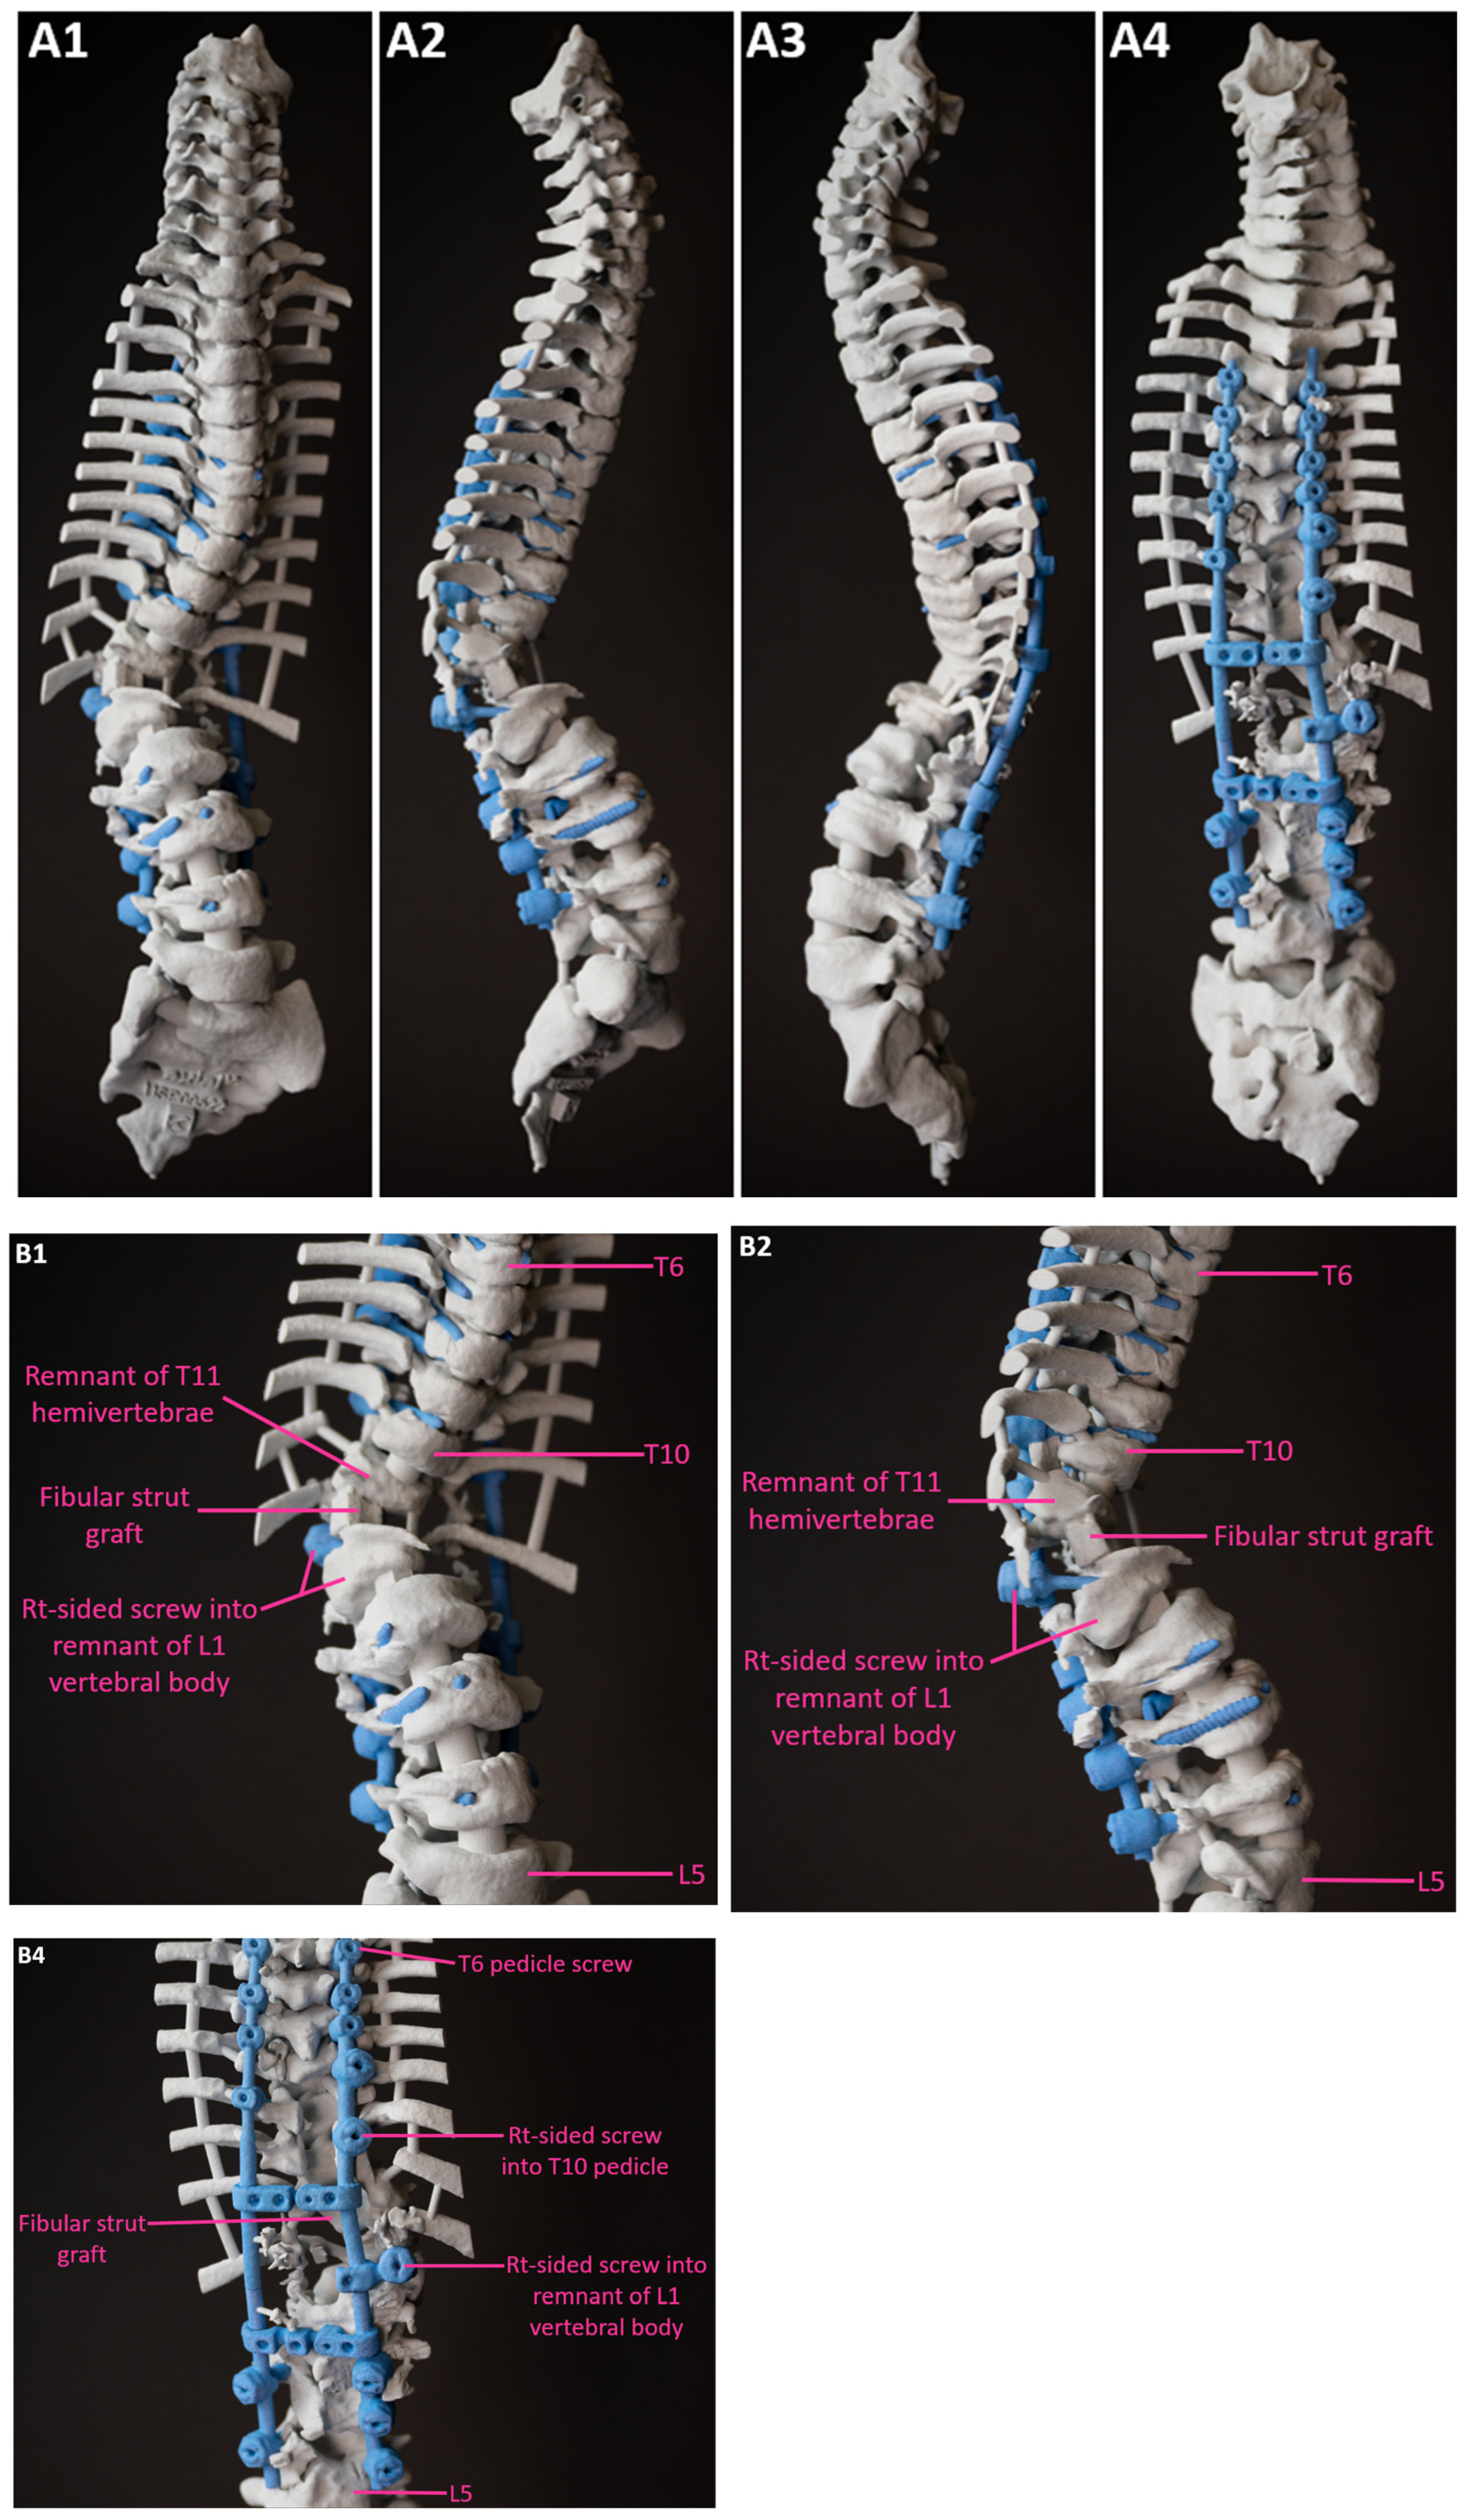

A 3D-printed model of the patient’s complete spine from C1 to the sacrum was obtained to facilitate preoperative surgical planning; osteotomies were also planned preoperatively on the model (Figure 6).

Figure 6.

Full length (A) & partial (thoracolumbar) (B) images of the 3D-printed spine biomodel with resection and osteotomy boundaries marked in red. 1–Anterior, 2–Right lateral, 3–Left lateral, and 4–Posterior views. * Incompletely formed/Congenitally malformed posterior elements. T—Thoracic; L—Lumbar.

Figure 11.

Full length (A) & partial (thoracolumbar) (B) images of the post-operative 3D spine biomodel. 1—Anterior, 2—Right lateral, 3—Left lateral, and 4—Posterior views. T—Thoracic; L—Lumbar.